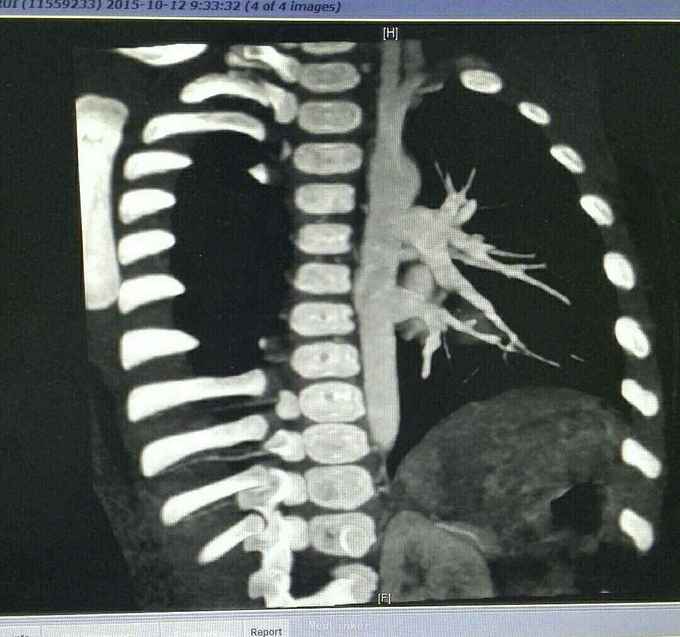

查体 生命体征平稳,口唇发绀,双肺呼吸音清,未闻及干湿性罗音,心律规整,于胸骨左缘可闻及杂音,腹部平软无压痛反跳痛,双下肢无水肿。 辅助检查结果 心脏彩超示 先天性心脏病 法乐氏四联症 肺动脉发育不良 左肺动脉 0.65mm,右肺动脉 0.49mm。 心脏CT检查结果示 先天性心脏病 法乐氏四联症 肺动脉发育不良

先天性心脏病 法乐氏四联症 治疗 患者入院后完善各项术前检查及准备,排除手术禁忌症后为患儿行跟手术治疗。 手术过程 全麻成功后,常规消毒,胸骨正中切口,常规建立体外循环,降温阻断升主动脉后,心脏停跳,切开右房,经卵圆孔放置左心引流,经右心室流出道切口,切除肥厚的隔束及壁束,切开肺动脉瓣交界处粘连,可通过9号探子,左右肺动脉可通过7号探子,取涤纶补片修补室间隔缺损,已带瓣牛心包补片加宽右室流出道,开放循环,心脏复跳,手术过程顺利,患者安反监护室。